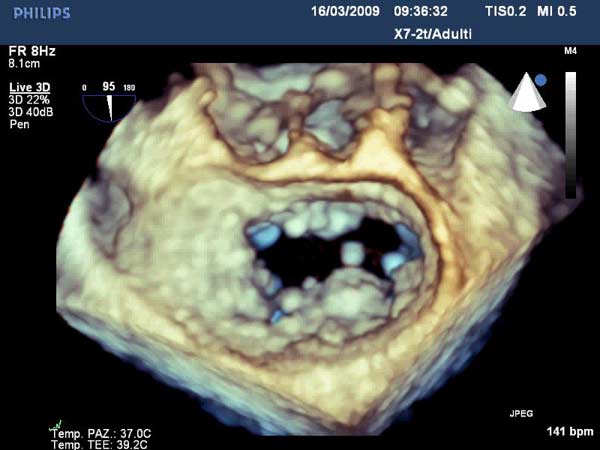

In absence of controlled clinical trial data which are forthcoming from the EVEREST II randomized study, the indications for the MitraClip therapy are currently based on registry experience and will evolve as the technique improves, experience is growing and the data to demonstrate efficacy and safety becomes available. At this time, the best indication for the MitraClip therapy is for symptomatic patients with clinically significant functional or degenerative MR who are at high or increased risk for open heart surgery. From a pure technical standpoint, the procedure so far has only been demonstrated in a subgroup of patients with specific anatomical characteristics which are summarized below and shown in Figure 3. Anatomic suitability is assessed by transesophageal echocardiography, and mitral regurgitation should originate from the central portion of the valve involving the A2-P2 segments, since the device is not ideal to work in the commissures at this time; the mechanism of MR can be either a prolapse/flail or MR due to restricted leaflet motion unrelated to rheumatic disease; the separation between the two leaflets at the site of regurgitation should be limited; severe annular dilatation and/or severe calcification should be absent or is relevant. In case of flail, the flail segment width should be less than 15 mm, and the flail gap less than 10 mm. Figure 4 is a 3D echo image of a patient with posterior leaflet prolapse selected for MitraClip therapy. In case of functional MR, the leaflets should have a minimal residual tissue available for coaptation with the MitraClip device. Figure 5 shows 2D color Doppler jet extension over the coaptation line at TEE short axis transgastric view, while Figure 6 shows the tenting area and the coaptation depth of a patient undergoing MitraClip implant.